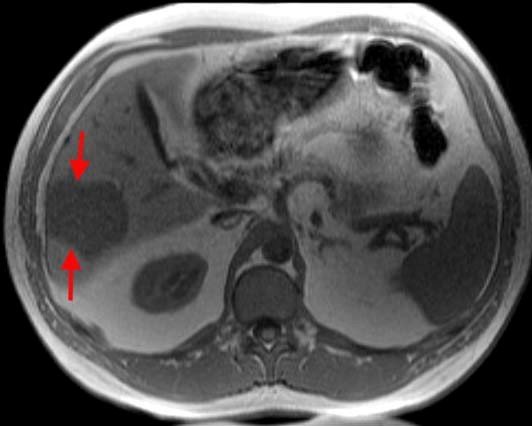

Əməliyyatdaxili ultrasəs müayinəsi 5MHz T tipli linear və ya əyri transdüser ilə aparılır (şək.1)

müayinəni aparan radioloq cərrahi sterilizasiyaya uyğun şəkildə əməliyyatda iştirak edir.

Transabdominal müayinələrdən fərqli olaraq US gel yerinə normal fizioloji məhluldan istifadə olunur. Ilk olaraq qaraciyər anatomik quruluşu müəyyən edilir (seqmentlər, damarların anatomiyası, öd yollarının variantları və s.) (şək.2)

Sonradan isə patoloji prosesin yerləşmə nahiyyəsi, yayılma dərəcəsi, damarlara olan münasibətini,invaziya dərəcəsini və  rezeksiya olunacaq sahənin adekvat olub olunmamasını müəyyən edilir.

Damarların anatomiyası və qan axının ölçülməsi rəngli Doppler müayinəsi ilə aparılır (şək.3).